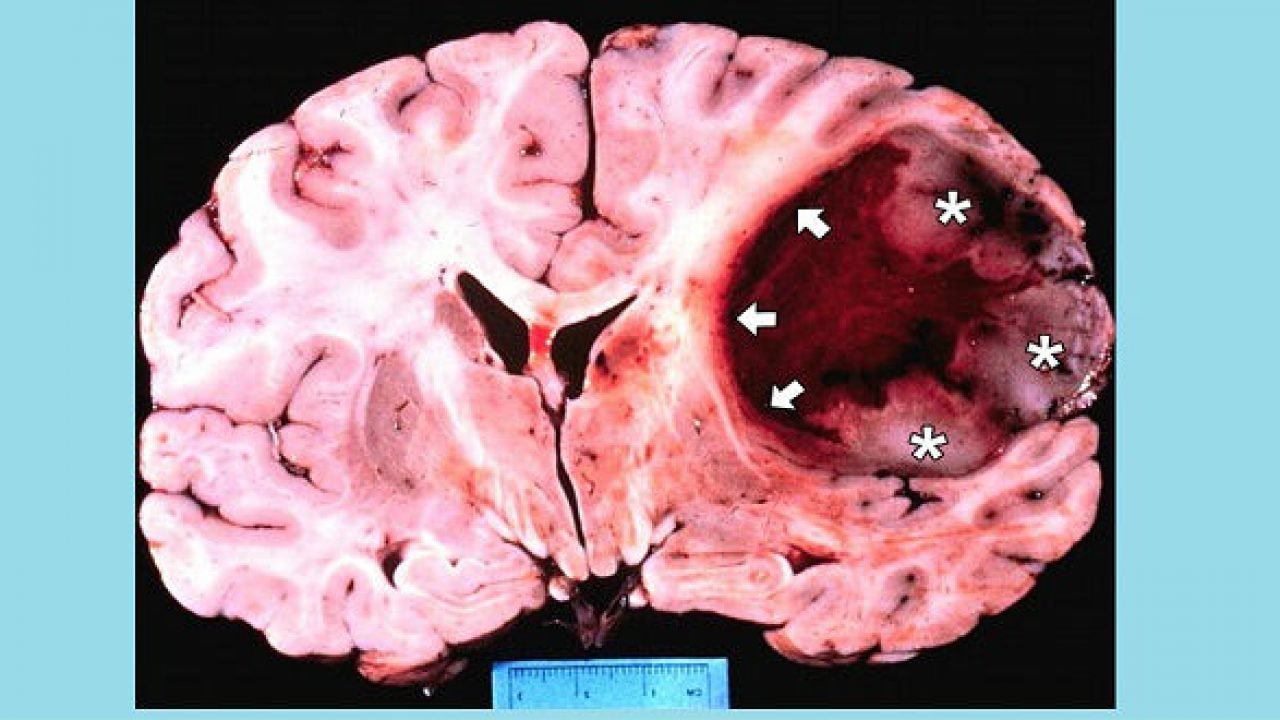

Hội chứng Turcot cũng là một biến thể của hội chứng FAP hoặc Lynch, chứ nó không phải là một tình trạng di truyền riêng biệt. Những người mắc phải hội chứng này thường có xu hướng có nhiều polyp đại tràng, tăng nguy cơ Ung thư đại trực tràng và tăng nguy cơ xuất hiện các khối u não. Hai loại U não hay gặp nhất trong Hội chứng Turcot đó là:

- U nguyên bào thần kinh đệm (Glioblastoma): là một dạng u tế bào hình sao, thường thấy ở các gia đình có đặc điểm của hội chứng Lynch.

- U trung thất: loại u này bắt đầu trong tiểu não, mặt sau của não. Loại này thường xảy ra ở trẻ em và thường được tìm thấy ở các gia đình có tình trạng của FAP.